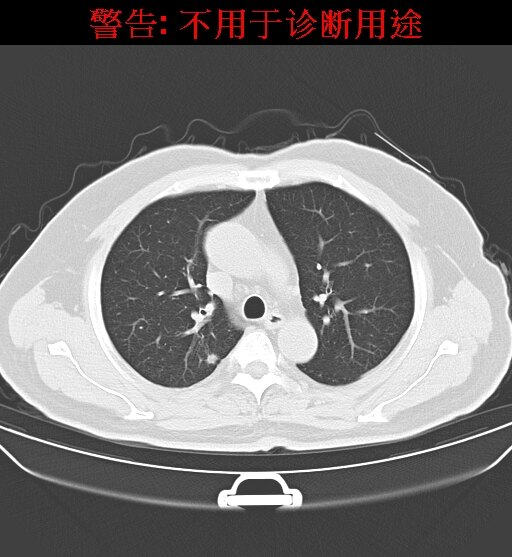

结节,只是影像学上的一个描述性名词,指的是病灶的大小,而不是病灶的性质。在影像检查中(CT或胸片)发现类圆形的直径小于3cm的病灶通常描述为结节灶,当直径小于1cm时常被描述为小结节,而直径小于0.5cm时就被称为微小结节。肺内结节或小结节分为良性、恶性两种。常见的肺内良性结节或小结节包括球形肺炎、结核球、错构瘤良性、纤维增生等,癌前病变为不典型腺瘤样增生,恶性病变则有可能是原发性肺癌或肺内转移癌。当然部分良性病变长时间之后也可能转化为恶性。根据结节的密度不同,可以分为纯磨玻璃结节、部分实性磨玻璃结节和纯实性结节。在这三类结节中,恶性病变分别占18%63%7%。初次CT检查发现的肺部小结节,80%-90%都是良性病变,但却要高度重视,因为仍有一定比例的早期肺癌,定期检查必不可少。

肺部结节检出率越来越高的原因主要在于,过去肺部体检主要是拍X光片,但X片对于小于1厘米的结节难以发现。现在,越来越多的单位改做低剂量肺部CT,连2毫米以上的结节都能发现,所以检出率就高了。CT在肺内病变中的诊断优势非常明显,CT通过显示组织横断面及三维结构图像进行诊查,有效避免了肺与心脏、纵隔、横膈等组织的重叠,能发现肺尖、脊柱旁、靠近胸膜、心脏后方等部位胸片难以发现的病灶。另外,低剂量CT筛查所产生的射线剂量很低,对人体的影响极低,对高危人群来说是体检的首选方法。那哪些人群属于肺癌筛查的高危人群呢?一般来说,年龄50岁以上并至少合并以下一项危险因素:(1)吸烟≥400*年,其中也包括曾经吸烟,但戒烟时间不足15年者;(2)被动吸烟者;(3)有职业暴露史(石棉、铍、铀、氡等接触者);(4)有恶性肿瘤病史或肺癌家族史;(5)有慢性阻塞性肺疾病(COPD)或弥漫性肺纤维化病史。